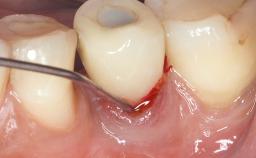

Surgical Management of Peri-Implantitis: Reconstructive Surgical Treatment with Three-Year Follow-up After Treatment

Despite anti-infective surgical treatment, some patients may experience recurrent infection and progressive bone loss requiring additional treatment. Removal of Implant Due to Recurrent Infection describes a conservative approach using an implant retrieval tool without the need for excessive bone removal or use of a trephine.

A 70-year-old female patient was referred by her general dentist to the periodontist for assessment and management of an infection associated with implant 36. The general dentist had noted suppuration on probing during examination.